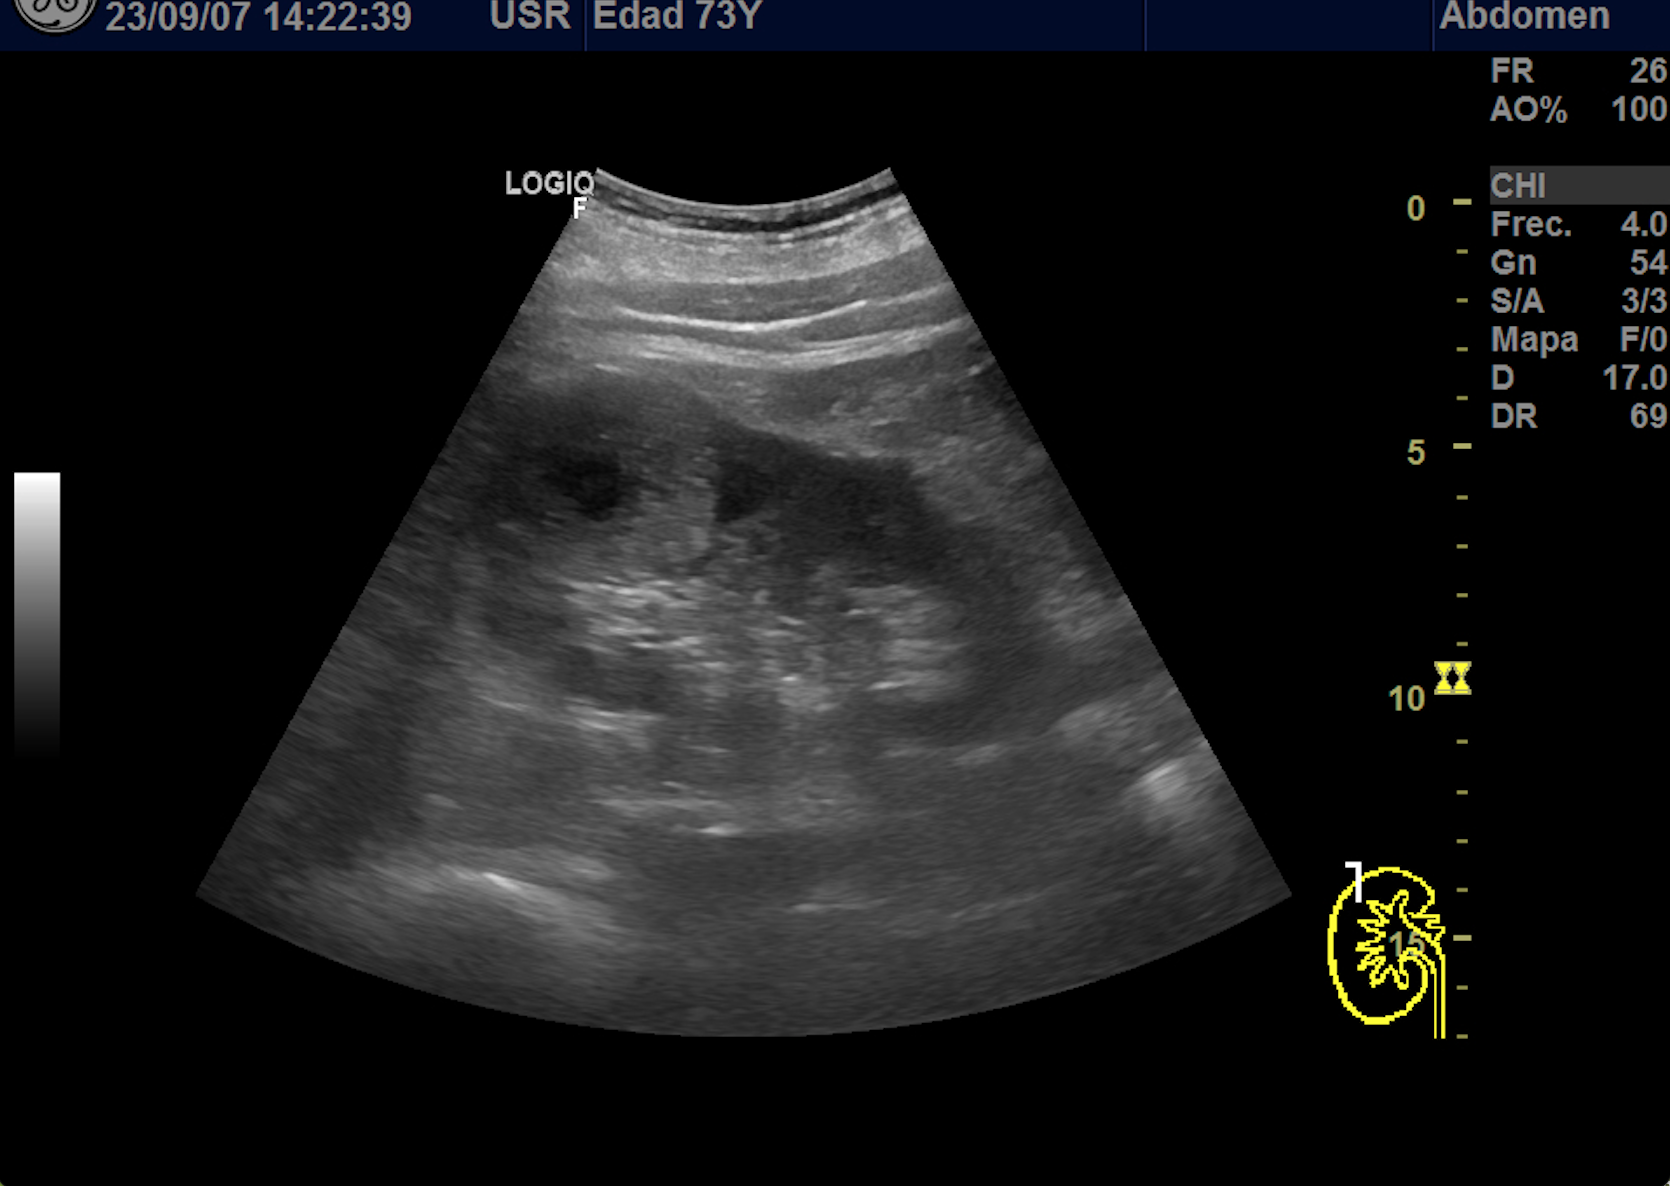

Hallazgos ecográficos

En polo superior de riñón derecho se observa una imagen redondeada, bien delimitada, isoecoica con un área central hipoecoica con vascularización periférica y central de 4,1 x 4,18 x 4,94 cm.

Dado el hallazgo de una masa renal se deriva a urología por el circuito de sospecha de malignidad.

Se le realiza un TAC abdomino-pélvico donde se observa a nivel de valva posterior del meso riñón derecho se observa una masa sólida de 5,1 x 4,9 x 5 cm compatible con proceso neoformativo, la lesión es exofítica de contornos bien definidos, tras contraste IV muestra un realce hipervascular con área central hipocaptante probablemente en relación con necrosis. Resto de estudio de extensión negativo.